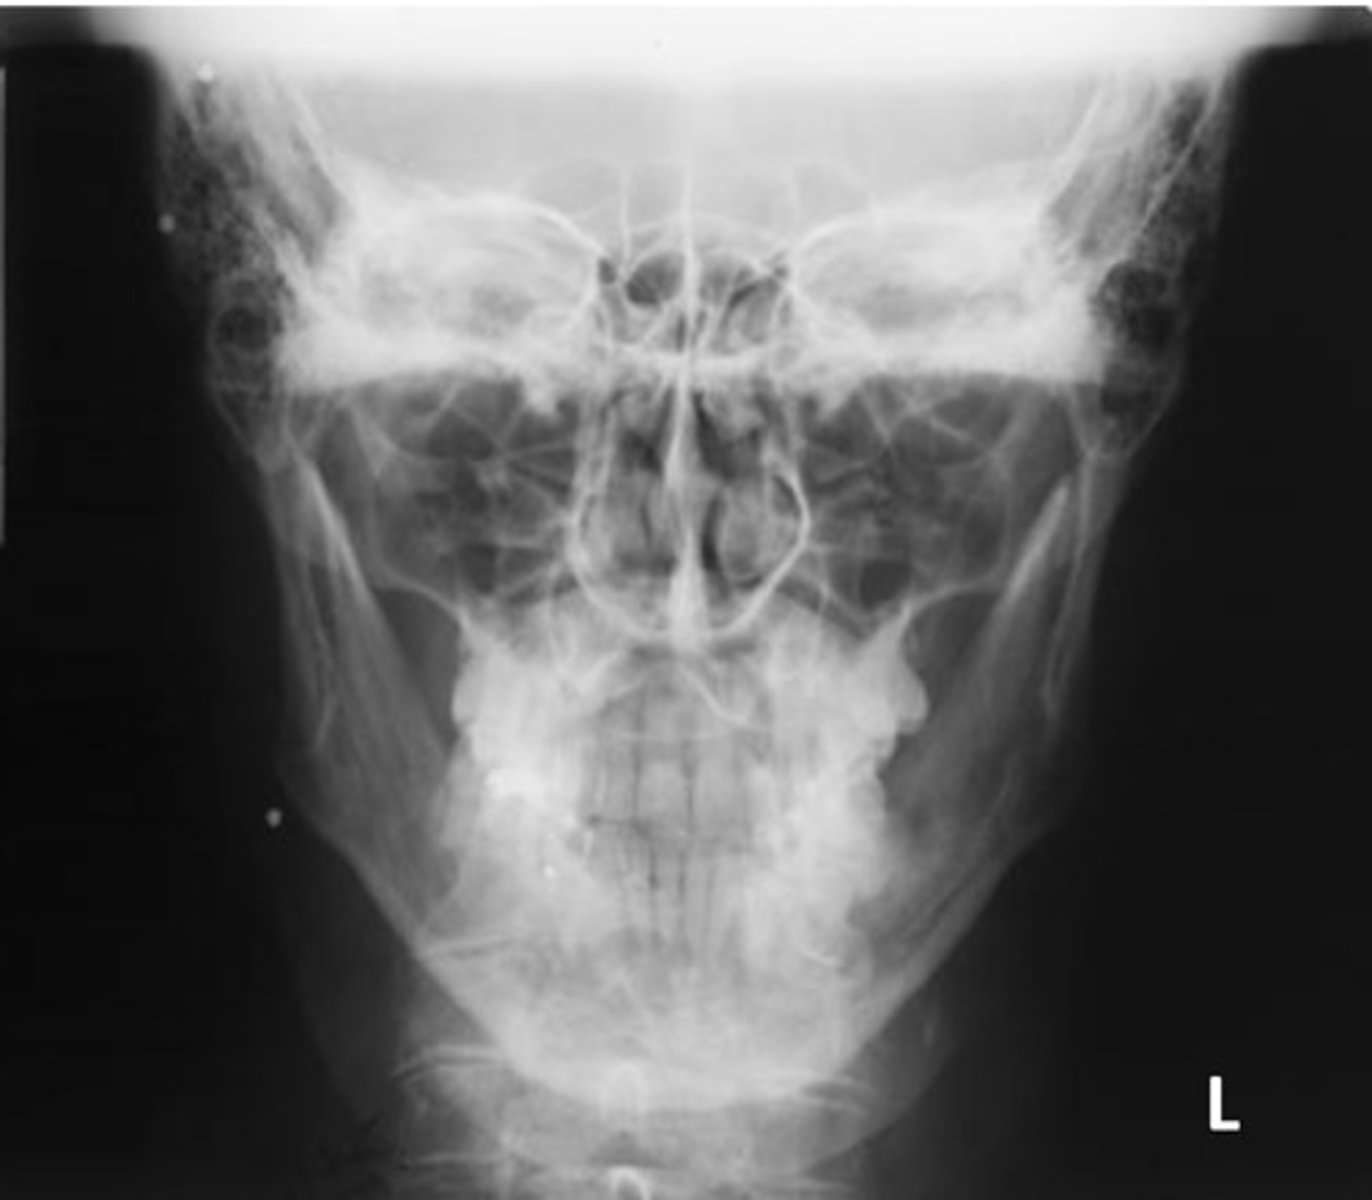

What projection and method is demonstrated?

Parietoacanthial (modified Waters)